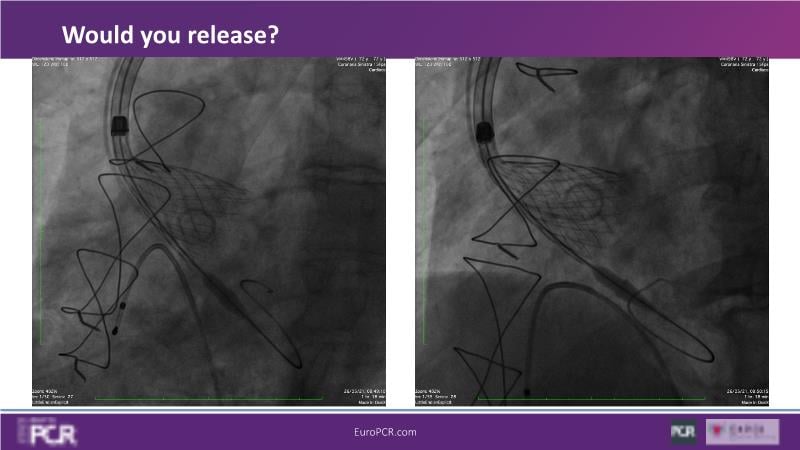

Discover the key factors to consider in selecting the optimal valve and implant technique for transcatheter aortic valve implantation (TAVI) to achieve optimal procedural outcomes. Gain insights into the impact of device choice and implantation technique on coronary access following TAVI and learn valuable strategies for tailoring your TAVI technique to complex scenarios, including bicuspid aortic valves, large and calcified anatomies, and ensuring coronary access.

- To learn how to tailor your TAVI technique to complex situations: bicuspid aortic valves, large, calcified anatomies and coronary access